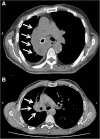

Background: Tracheobronchial malignant stenosis is a life-threatening condition which may cause recurrent infections due to lung atelectasis. Despite immunotherapy is less toxic than standard chemotherapy, recurrent lung infections may represent a challenge for this treatment. We report a clinical case of a patient with metastatic squamous cell carcinoma suffering from pulmonary infections due to central airway obstruction who underwent endoscopic recanalization followed by immunotherapy. VSports手机版.

Case presentation: A 64 year-old man was referred to our attention for the management of metastatic squamous cell carcinoma obstructing the right main bronchus with recurrent pulmonary infections. Patient exhibited strong positive PD-L1 expression (> 50%) V体育安卓版. Advanced disease stage contraindicated surgical treatment. Although therapy with immune check point inhibitors was indicated as first-line treatment, recurrent pulmonary infections made it unfeasible. Therefore, we planned a combined approach including endoscopic recanalization of central airway in order to resolve lung atelectasis, and lung infection followed by immunotherapy treatment with pembrolizumab in order to avoid local and systemic disease progression. .

Conclusions: At 16-week follow-up, the patient was alive in stable disease with improvement of clinical condition and no signs of lung infection. V体育ios版.